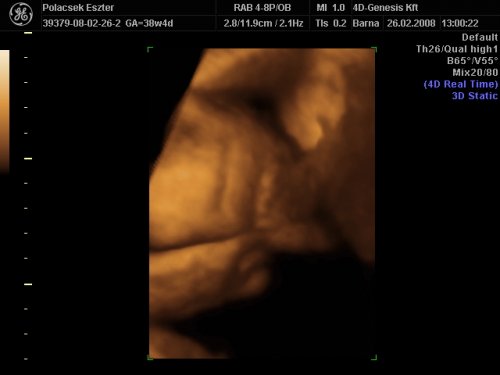

S ha már imígyen esett, hát jól megnéztük egymás -közel sem egy súlycsoportos- dedjét, sőt, lehetőségünk lett volna megtekinteni egymás mélyebb ivari útjait is, ettől azonban, jóérzésünk maradékának birtokában eltekintettünk.

- Mindkét ded gyönyörű és a mai napon kivételes módon mutogatni kívánta magát

- Mindkét kispasas oltári, pirongató méretű zacsival rendelkezik, amelyet (már a sajátját) Norton bal alsó madárfogással vadul szorongat

Képeket mindketten teszünk fel még ma.